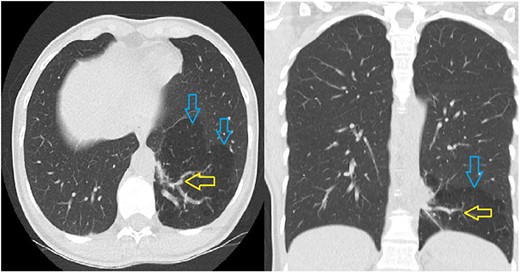

The 39-year-old female patient was referred to us after a PS was found incidentally on a thoracic CT scan. This scan had been performed due to a suspected collagenosis, which was confirmed thereafter. However, PS was asymptomatic so far. Computed tomography showed a lesion of 8.7 cm × 9.8 cm × cc 7.7 cm not being in communication with the tracheobronchial system. An aberrant artery was branching from the thoracic aorta (Fig. 1). She was diagnosed with intralobar PS and minimally invasive surgery with the help of a robotic daVinci X System was indicated.

The CT scan shows a hypodense part in the left lower lobe (blue arrows) with an aberrant artery (yellow arrows) arising from the thoracic aorta.